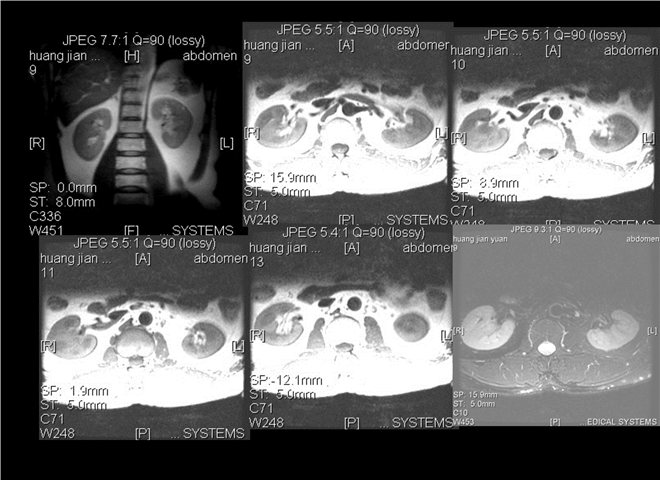

13_CT增强扫描